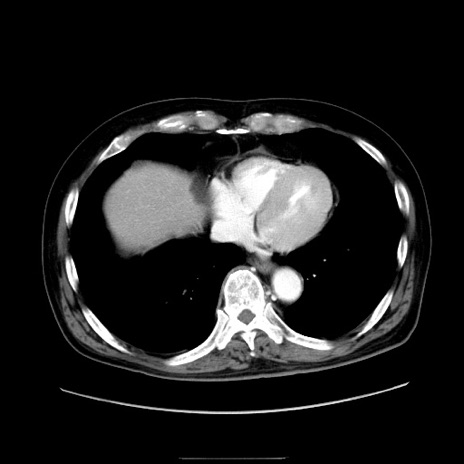

冠状断像

症例30(横断像)

【症例】80歳代男性

【現病歴】約6時間前から臍下部痛が出現。次第に腹部膨隆・背部痛も生じてきたため来院。背部痛の場所は変化しない。

【身体所見】意識清明、BT 36.3℃、BP  131/87mmHg、P 87bpm、SpO2 100%(RA)、臍周囲自発痛・圧痛あり、反跳痛なし、自発痛部位に一致して板状硬あり、腹部膨隆、腸雑音減弱、CVA tenderness両側陰性。